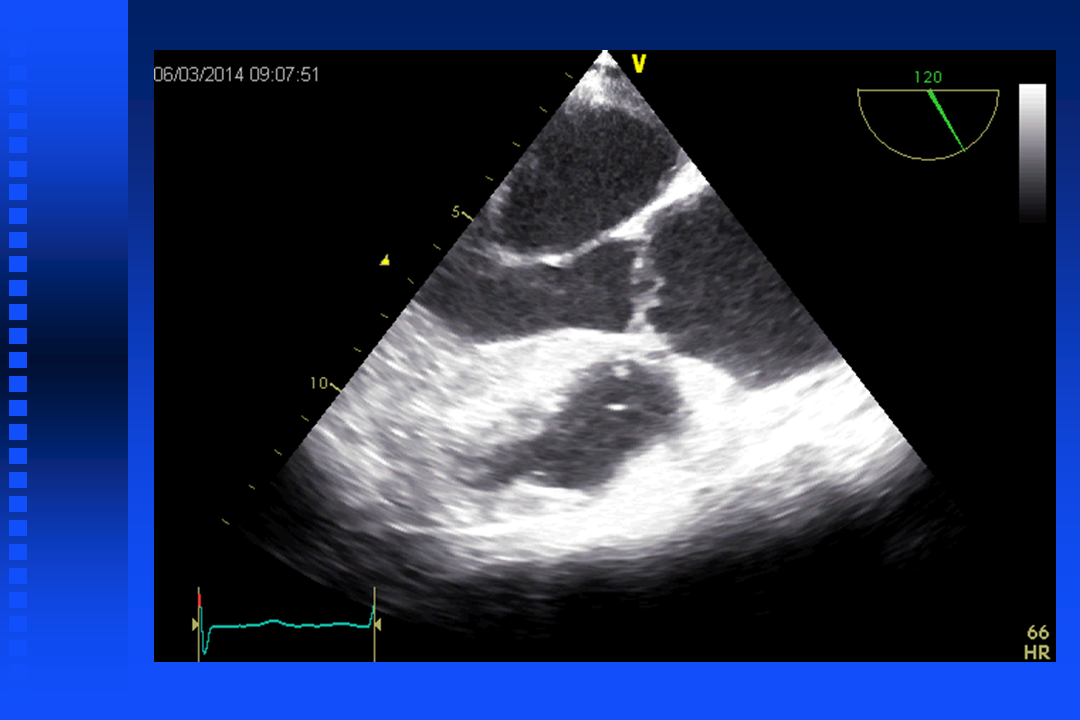

Echocardiography

Anesthesia for Coronary Surgery

Transesophageal echocardiography (TEE probe) is always used to detect cardiac function and regional wall motion abnormalities. Be sure to check for swallowing dysfunction, as TEE is contraindicated in cases of esophageal stricture, as the TEE probe could cause damage.

- TEE – for intraoperative ischemia or pronounced hemodynamic instability

- TEE – for pronounced hemodynamic instability

- TEE: “Recommended if acute and severe hemodynamic instability develops perioperatively” (Class I)